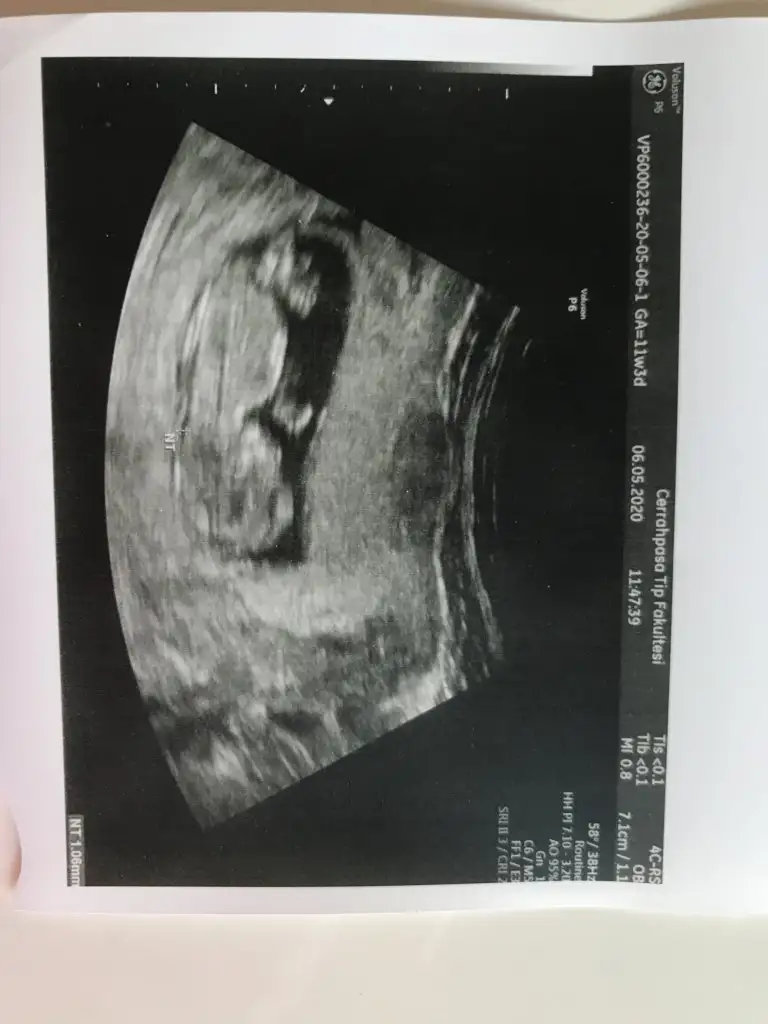

resim yokArkadaşlar 11 hafta 3 günlük hamileyim rica etsem cinsiyet tahmini yapabilir misiniz?

Kıza benzettimArkadaşlar 11 hafta 3 günlük hamileyim rica etsem cinsiyet tahmini yapabilir misiniz? Resim ekleyememişim şimdi ekledim şimdiden teşekkürler

Kız gibiArkadaşlar 11 hafta 3 günlük hamileyim rica etsem cinsiyet tahmini yapabilir misiniz? Resim ekleyememişim şimdi ekledim şimdiden teşekkürler

Kesinleştimi erkek olduguArkadaşlar 11 hafta 3 günlük hamileyim rica etsem cinsiyet tahmini yapabilir misiniz? Resim ekleyememişim şimdi ekledim şimdiden teşekkürler